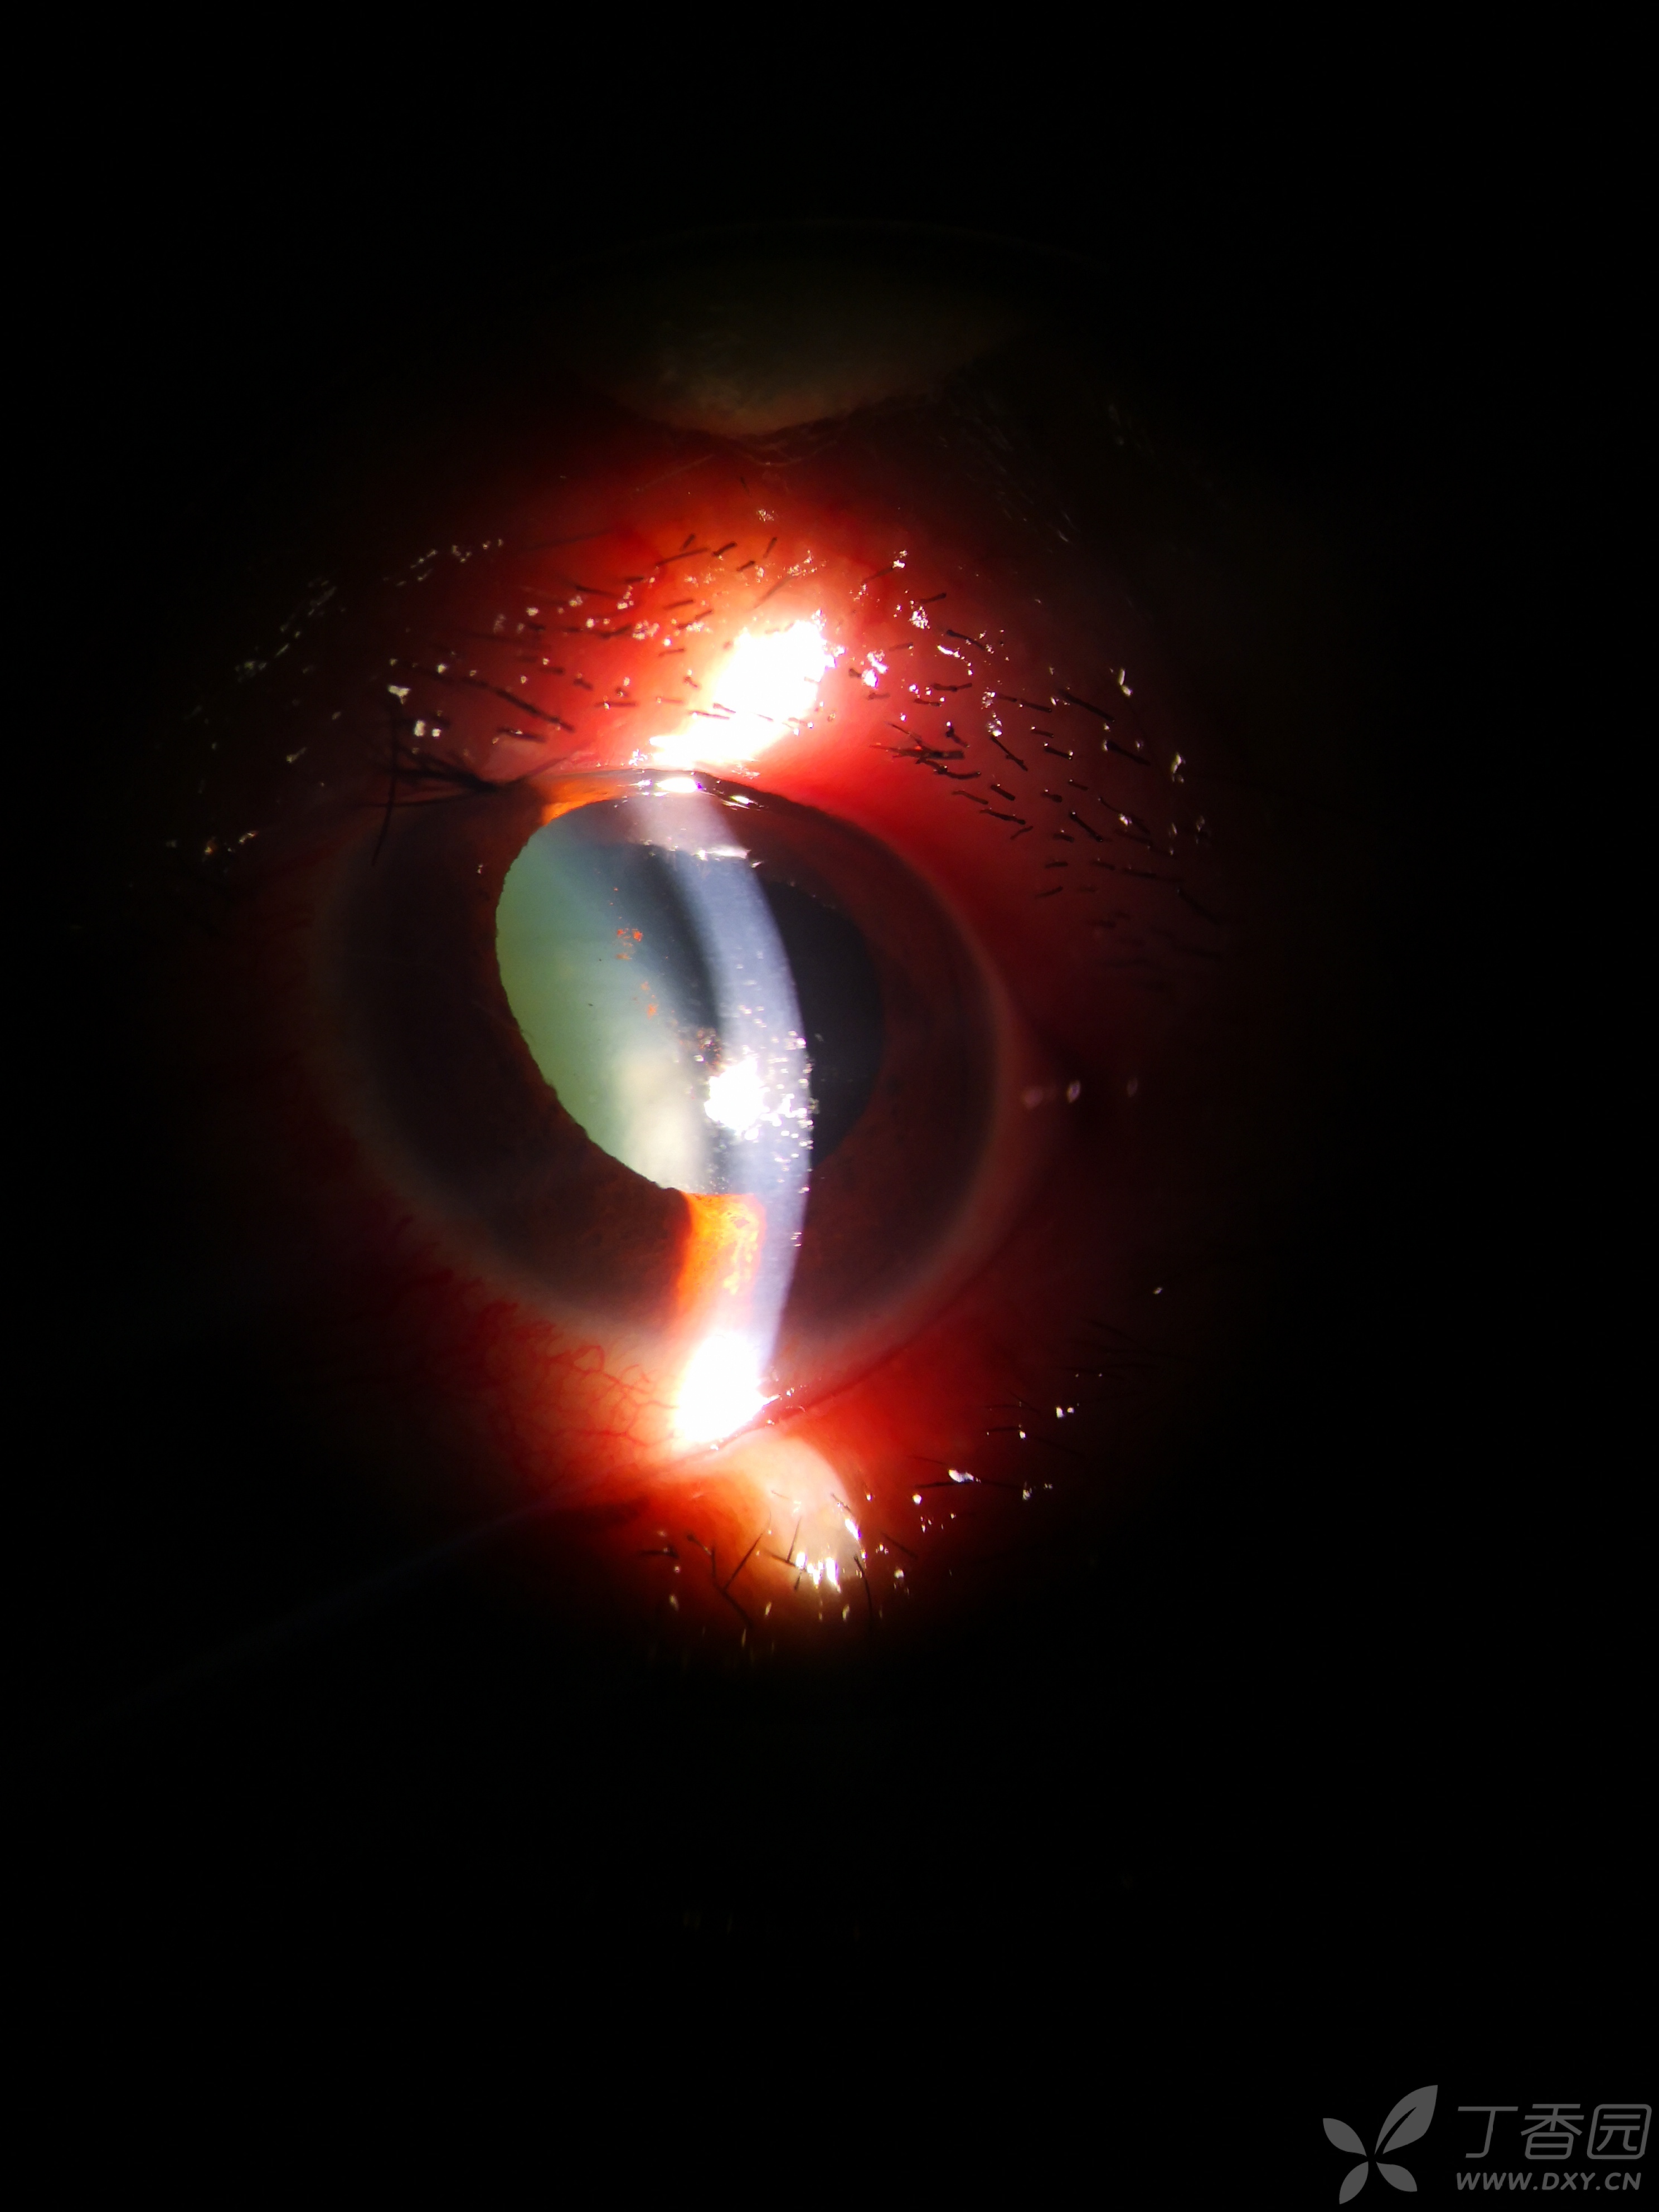

青光眼小梁根切术术后浅前房,低眼压,大神各抒己见,百家争鸣下呗.